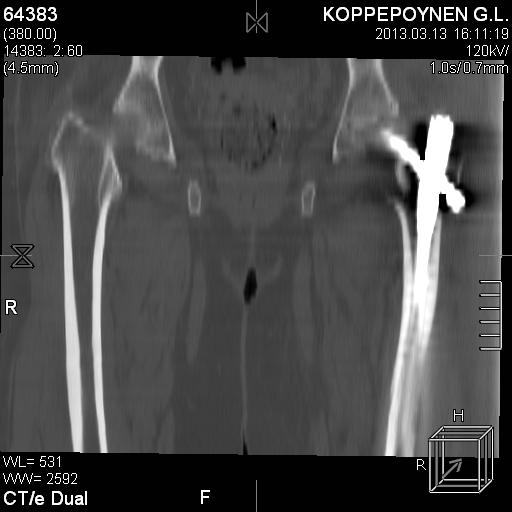

Делали КТ после операции.

Непонятно, на какой вопрос с помощью КТ хотели получить ответ? IMHO это было ненужное исследование, все проблемы были видны на обычном снимке. А что на второй проекции? Где аксиальная или профиль?